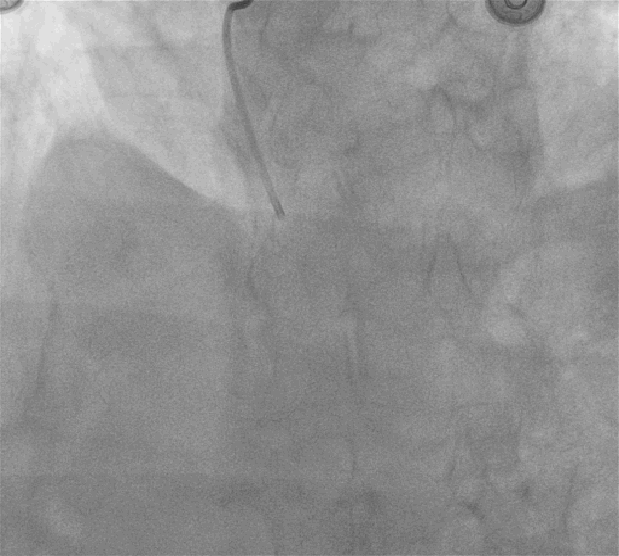

左图:AL1.0指引导管到位后,Sion导丝顺利送至右冠脉远段,迪马克2.5*15mm球囊到位困难,采用双导丝技术,球囊顺利到位后给予预扩张(10atm)。

右图:病变部位预扩后残余狭窄小于30%,病变部位未见明显夹层及撕裂,给予药物球囊鼎科2.5*20mm病变部位释放(8atm,60S)。

反复多体位造影提示:病变部位残余狭窄小于30%,未见明显夹层及撕裂,TiMi血流III级;